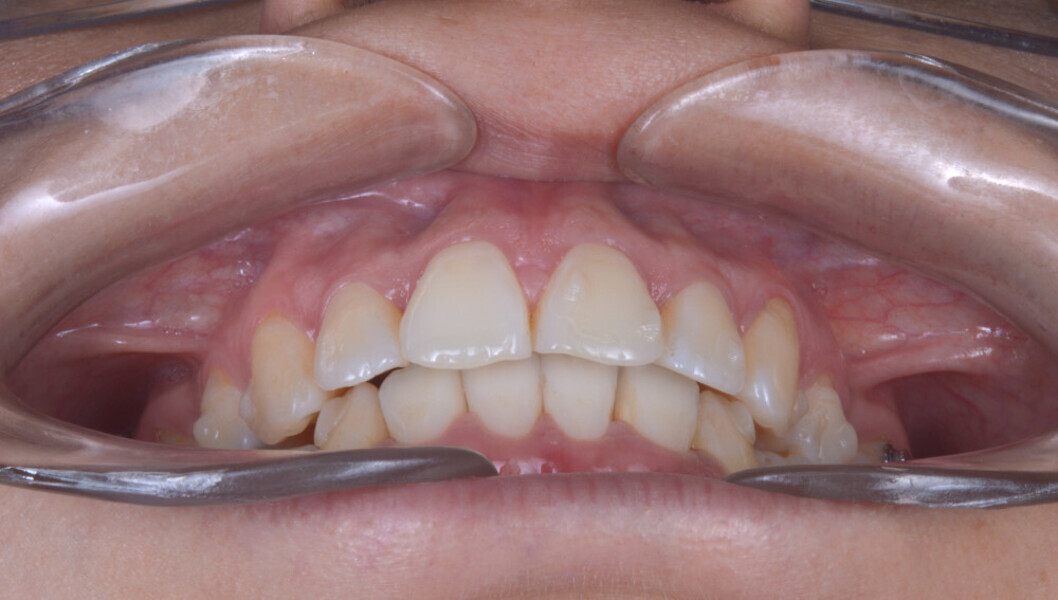

A 35-year-old female patient presented with crowding, muscle and joint pain, and headaches upon awakening. Examination found a skeletal Class I with crowding and bimaxillary protrusion. Facial examination showed a convex profile with protruded lips and a square face shape, intensified on smiling (Figs. 1–4). She reported bruxism, and bilateral masseteric hypertrophy was observed, but there was no alteration of the temporomandibular joints.

Before the aligner treatment began, the maxillary and mandibular second premolars were extracted to create space. With orthodontic treatment, distalisation of the anterior teeth was achieved by employing maximum mandibular anchorage and moderate maxillary anchorage (Figs. 5–7). At the end of the treatment, a stable bilateral Class I occlusion had been achieved, as well as normal inclination and retrusion of the anterior teeth, consequently improving the profile (Figs. 8–10).